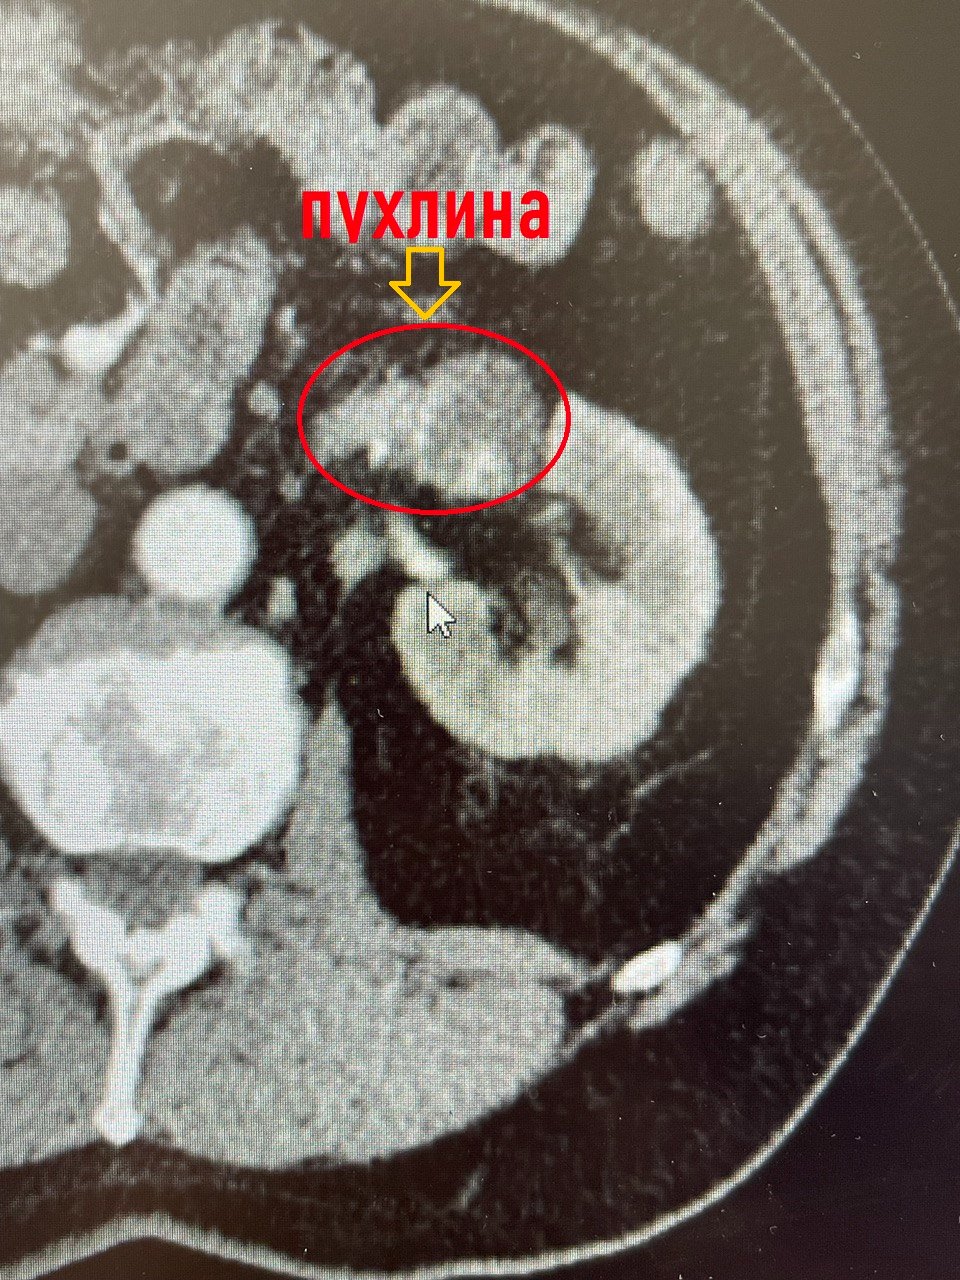

Обстеження на комп’ютерному томографі показали наявність в нирці коралоподібного каменя розміром 38х28 міліметрів та доброякісного пухлинного утвору до 3 сантиметрів у діаметрі з неоднорідним кровотоком у центрі, який знаходився на судинній ніжці лівої нирки.